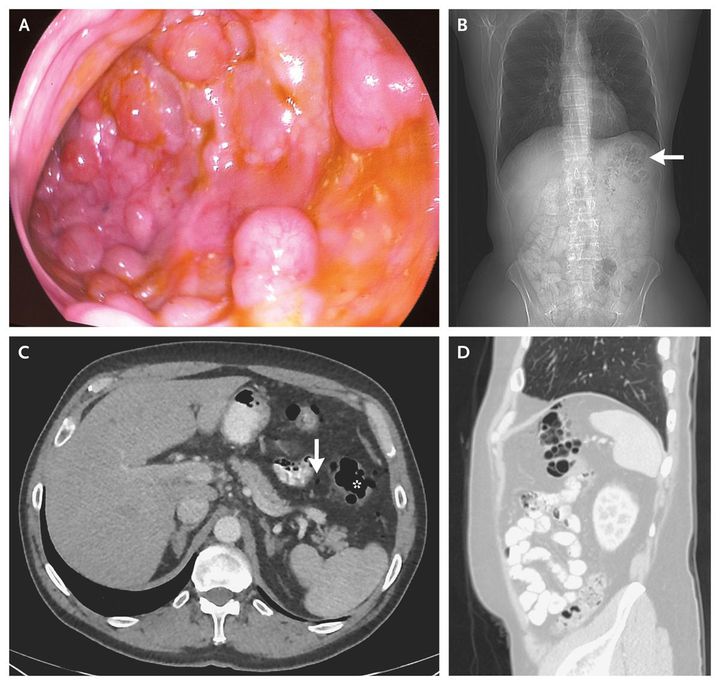

A 63-year-old man presented for a screening colonoscopy. During the colonoscopy, several submucosal polypoid lesions, 3 to 8 mm in diameter, were noted in the splenic flexure. Since the lesions were easily indented with gentle pressure and had a bluish hue, pneumatosis intestinalis was suspected (Panel A). When the lesions were punctured, they became deflated, supporting the diagnosis (see video). Computed tomography revealed multiple air pockets in the intestinal wall at the splenic flexure (Panel B, arrow; Panel C, asterisk; and Panel D) and some free intraperitoneal air (Panel C, arrow). The results of histopathological inspection of an endoscopic-biopsy specimen were consistent with pneumatosis intestinalis. Pneumatosis intestinalis is diagnosed by the presence of air pockets in the intestinal wall. In certain cases, pneumatosis intestinalis may be considered a surrogate marker for intestinal ischemia and impending perforation. However, the condition may also occur in a benign context and is no longer considered a disease but rather a sign, and its significance needs to be considered in accordance with each patient's clinical context. This patient required no specific treatment and has remained asymptomatic.